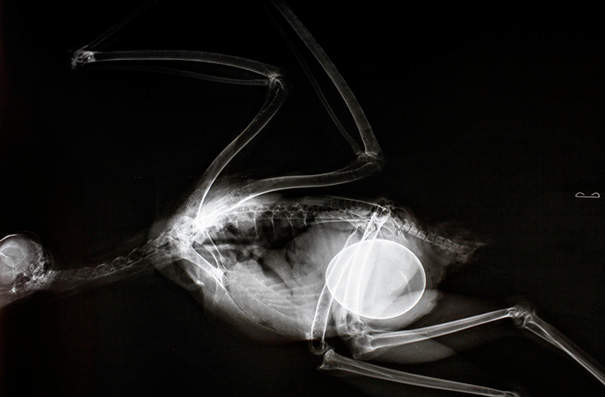

紅尾鵟

▼

圖片來自:boredpanda